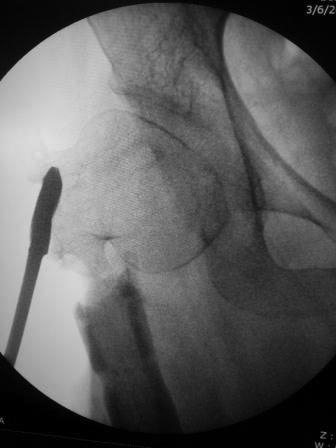

Уважаемые коллеги. Больная оперирована 06.03.15г клинок был сломан, и пока его с трудом удалили, от неполноценного вертела почти ничего не осталось, сломанный шуруп тоже удален, шейка совсем короткая, , ШДУ около 95гр, из-за сильного остеопороза при сверление в положении чуть вальгуса наружная стенка крошится , и еще что интересно при первой операции головка бедра оказалось фиксирована в положении ретроверсии примерно 10-15 гр.. и с трудом удалось выпрямить головку и шейку до 0 гр. , укорочение было чуть больше 1см , п/о -2см, пока фиксация - гипсовый сапожок с деротатором. Дальше как быть? Может временно фиксировать кокситной повязкой( канда каст)?